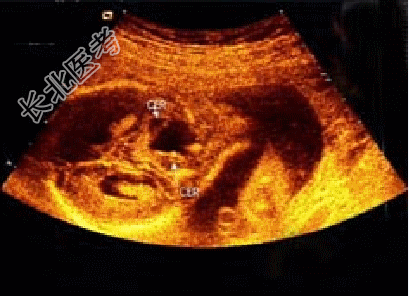

- 单项选择题胎儿头颅部超声检查如图,最可能诊断为( )

A、小脑蚓部缺损

B、正常声像图

C、先天性蛛网膜囊肿

D、脑积水

E、孔洞脑